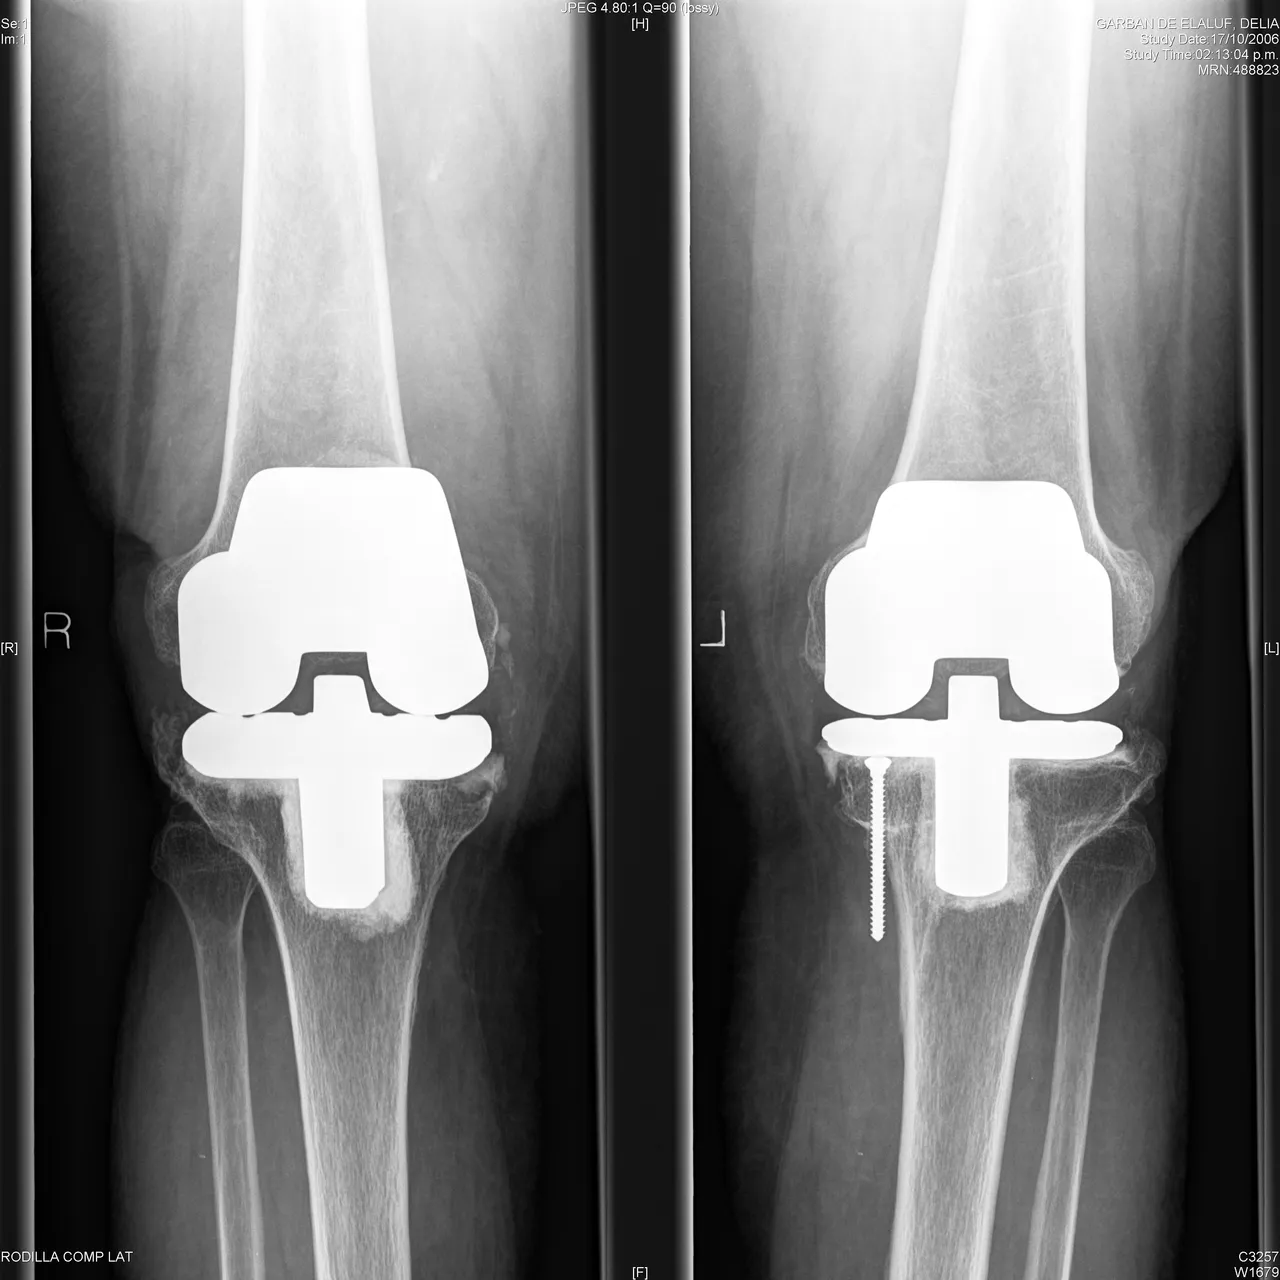

There are studies that compare the placement or not of patellar component in bilateral arthroplasties, with similar results, only that when no patellar component was placed, they presented pain when standing or going up and down stairs; our patients did not receive the patellar component. The type of system to be used was compared in Switzerland, analyzing the advantages of each one; no long-term differences were found; yes with asymmetries in the movement of the patient in the mentioned systems. We consider that the system used is the one the surgeon handles best; the advantages provided by new systems on the market are recognized beforehand, purifying the surgical time for their placement.

Performing total bilateral knee replacements is a reproducible option and we can suggest that practicing them consecutively is what in the group presented the best results, is the most balanced method in terms of its advantages and disadvantages, likewise, we did not find an increase in surgical risk or major complications.